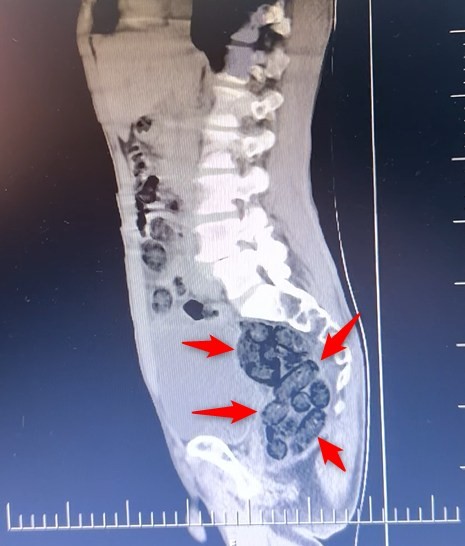

Batman’da durdurulan otobüsteki yabancı şahsın midesinden 64 parça uyuşturucu maddesi metamfetamin çıktı.

Durumundan şüphelenilen yabancı uyruklu bir yolcu üzerinde arama yapıldı. Yapılan incelemeler sonucunda yabancı uyruklu şahsın midesinde 64 Parça halinde toplam 472 gram uyuşturucu maddesi metamfetamin olduğu belirlendi.

Gözaltına alınan şahsın midesindeki uyuşturucu madde çıkartıldı. Emniyetteki işlemlerinin ardından adliye sevk edilen şahıs, çıkarıldığı mahkemece tutuklanarak cezaevine gönderildi.